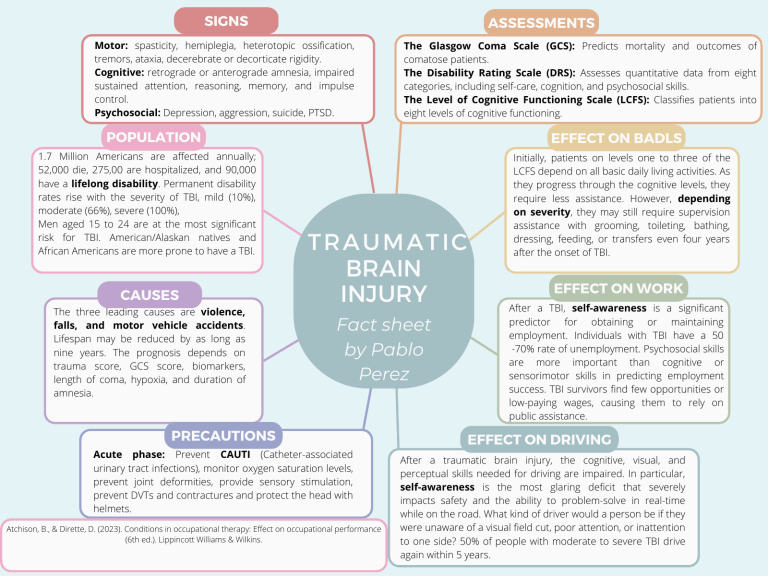

Traumatic Brain Injury Fact Sheet